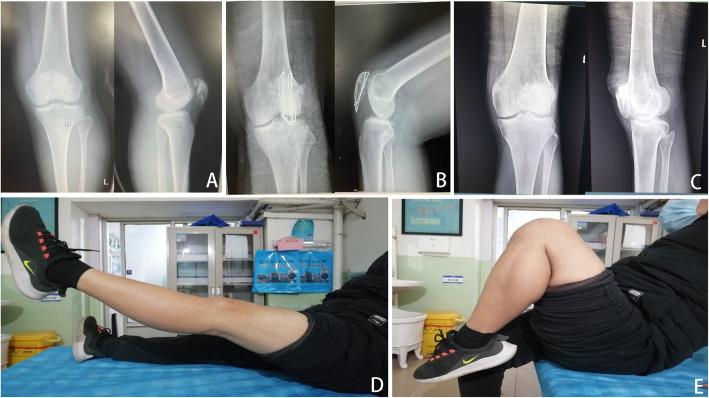

Between January 1987 and December 2003, this retrospective study included a total of 35 patients (mean age, 51.4±16.8 years) with a minimum of 10 years follow-up period, comprising 29 males and 6 females, who were divided into the total patellectomy group (17 patients) or the open reduction and internal fixation (ORIF) group (18 patients) in the Third Affiliated Hospital of Hebei Medical University. We retrospectively collected patient demographics and data on the type of trauma, fracture type, and postoperative complications. Clinical outcomes including knee range of motion (ROM), 36-Item Short-Form Health Survey (SF-36) score [including physical component score (PCS) and mental component score (MCS)], Knee Injury and Osteoarthritis Outcome Score (KOOS), and Kujala score were evaluated and compared between the two groups. Biodex System dynamometer was used to quantitatively evaluate quadriceps femoris muscle power following measurement of peak torque.

RESULTS

The mean follow-up periods of the total patellectomy group and the ORIF group were 17.2±5.6 and 16.8±4.9 years, respectively. There were no significant differences between the two groups of patient demographics in terms of the number of patients, age, sex, injury side, time to surgery, type of trauma, and fracture classification (p>0.05). Total patellectomy was comparable to osteosynthesis with tension band wiring in terms of ROM [injured knee: 120.4±3.1° vs 118.6±3.3°; uninjured knee: 126.5±2.8° vs 127.3±1.7°; both p>0.05], peak torque [Injured knee: 96.2±2.3 vs 97.3±2.6, N· m; Uninjured knee: 107.6±2.1 vs 106.3±1.8, N· m; both p>0.05], SF-36 score [PCS: 64.1±18.0 vs 61.5±17.9; MCS: 55.1±13.8 vs 54.3±12.4; both p>0.05], KOOS score [76.3±12.1 vs 73.4±11.7; p>0.05], and Kujala score [67.6±11.8 vs 70.8±11.9; p>0.05] at the final follow-up, while total patellectomy had significantly shorter operation time than ORIF group (47.5±12.1 vs 68.8±22.3, min, p<0.05). In the total patellectomy group, complications occurred in 6 of 17 cases (35.3%), and all occurred with calcification. In the ORIF group, complications occurred in 12 of 18 cases (66.7%), including 2 cases of infection (11.1%), 1 case of non-union (5.6%), 2 cases of implant failure (11.1%), 2 cases of soft tissue irritation (11.1%), and 5 cases of patellofemoral arthritis (27.8%).

CONCLUSIONS

Total patellectomy technique was a safe and reliable alternative treatment for treating patients with highly comminuted patella fractures when anatomically reduction and rigid fixation were difficult, although it caused relatively higher rates of calcification.